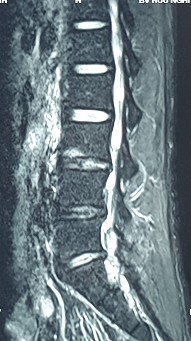

2. Hình ảnh khảo sát dẫn truyền thần kinh, điện cơ đồ và MRI (thực hiện trên mẫu nghiên cứu: bệnh nhân Hoàng Đình H., mã số bệnh nhân 1010320).

Bệnh nhân H., khi khám lâm sàng có biểu hiện tổn thương rễ thần kinh L4, L5, S1. Kết quả xét nghiệm điện cơ thấy: dẫn truyền thần kinh thấy mất phản xạ H, nhưng kết quả khi điện cơ kim có biểu hiện tổn thương rễ thần kinh L5 . Kết quả chụp cộng hưởng từ là tổn thương thoát vị L4 – L5, L5 – S1. Như vậy, trên bệnh nhân này vị trí tổn thương thực tế khi kết hợp phối hợp giữa khám lâm sàng, chẩn đoán hình ảnh và chẩn đoán chức năng là vị trí rễ thần kinh L5.

Hình ảnh thoát vị đĩa đệm trên phim chụp MRI.